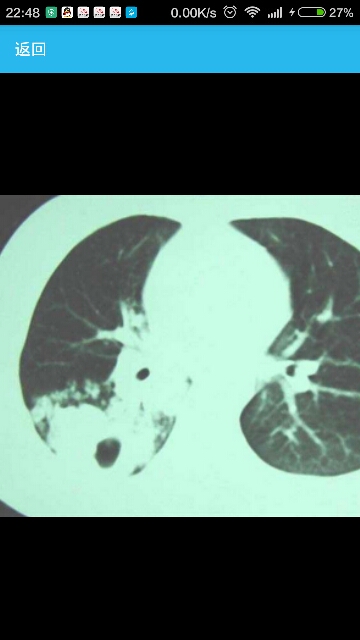

患者女性,15岁,因咳嗽、咯痰4个月入院。 病史4月前感冒后出现咳嗽、咯大量黄脓痰,无咯血,自服克林霉素1周无效。逐渐出现发热,38.5℃±,伴右侧胸痛。院查:ESR30mm/h,抗结核抗体(-),支原体抗体1:160,口服克拉霉素无效来我院。 临床表现消瘦,右下肺呼吸音减低。 辅助检查PPD:硬结15×15mm.支原体抗体:1:640气管镜检查示:右下叶背段开口环形狭窄,粘膜充血水肿。气管镜病理:上皮细胞巢,可见凝固性坏死。抗酸杆菌染色(+) 诊断:肺结核